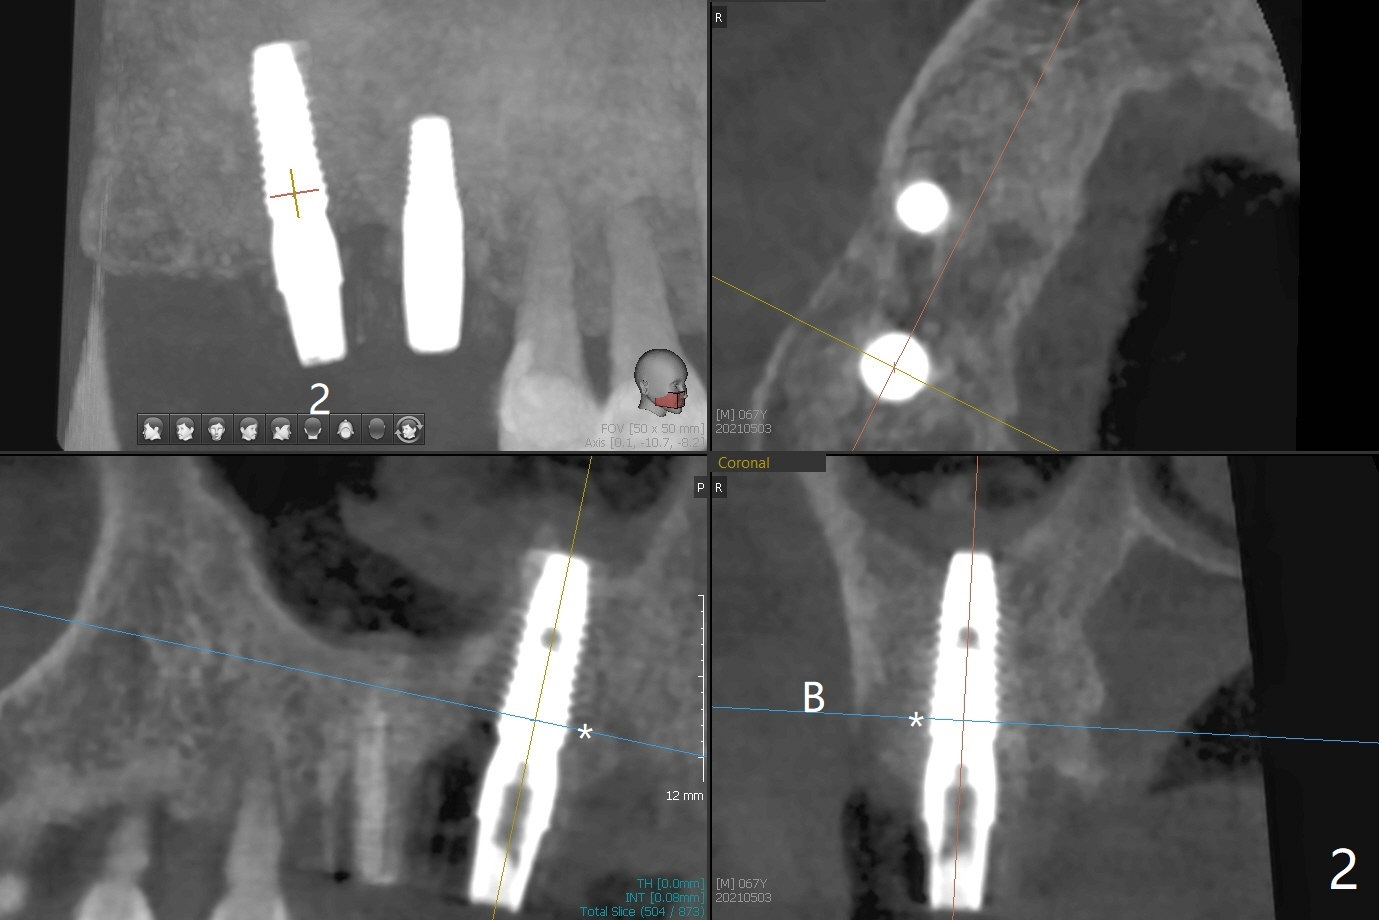

尽管2号牙植体比设计长,上颌窦提升顺利(图一,二)。虽然3号牙植体颊侧仍有骨质(图三:B),由于近中骨质多,徒手植入时植体远中偏移(图一:红箭头)。术后一个月树脂敷料撤除,2号牙牙槽窝,3号牙伤口愈合(图四)。